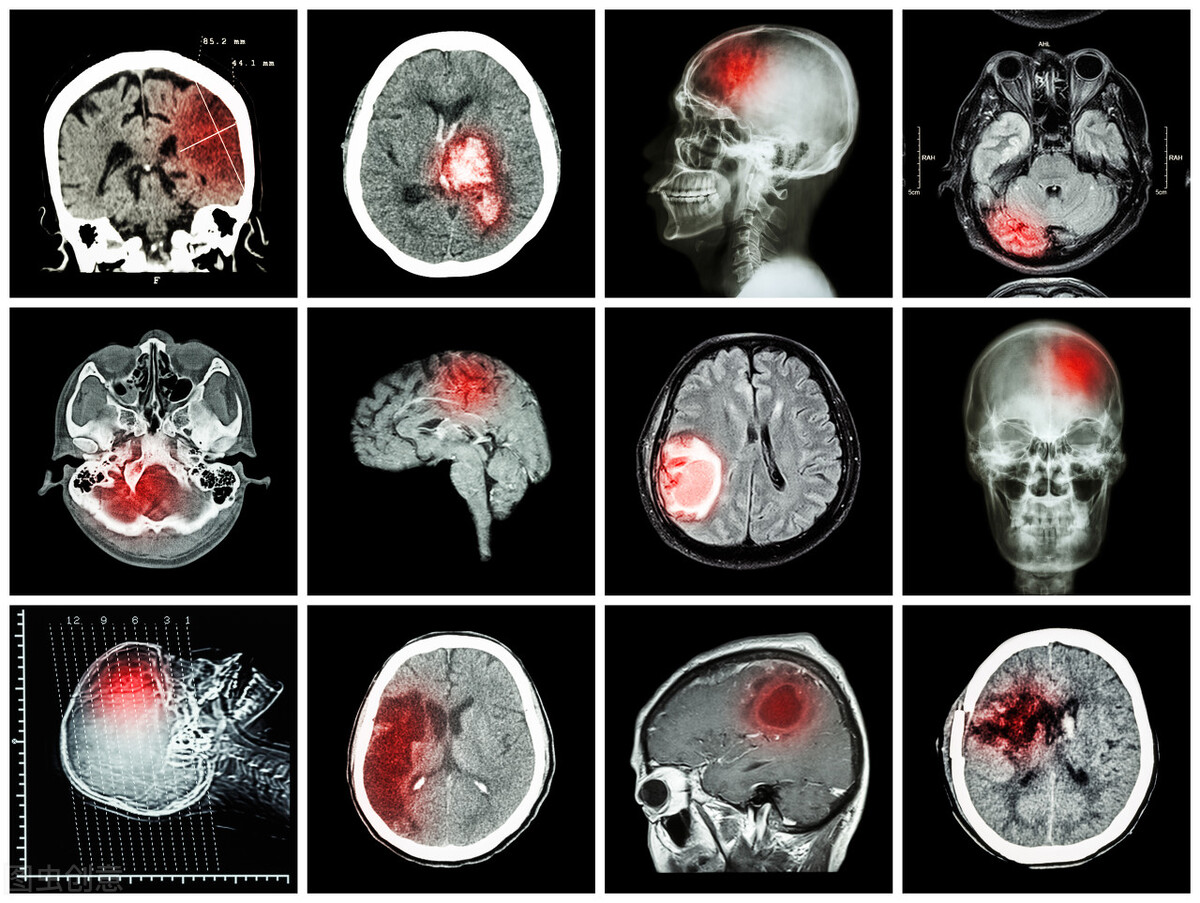

这个地方如果出现狭窄堵塞,脑部供血就可能不足,从而引起头晕、乏力等症状,还可能诱发脑梗出现。

肯定会。因为本身有斑块之后,斑块情况如果不稳定,它就有破的可能性,那么局部就有血栓。一旦有血栓形成,那么到脑子这个就梗了。